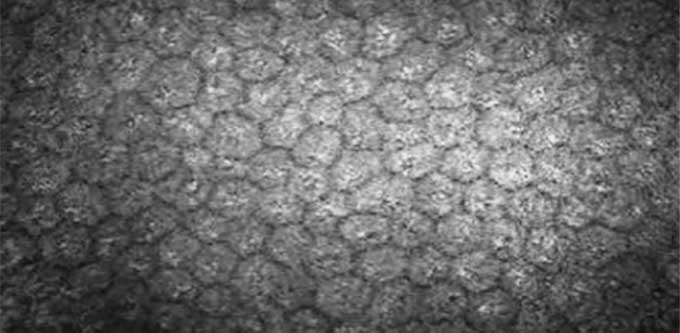

正常的角膜内皮是单层大小均匀的细胞,主要呈六边形。当某区域内皮细胞凋亡,其相邻细胞会相应增大并移行填充该区域。

角膜内皮细胞